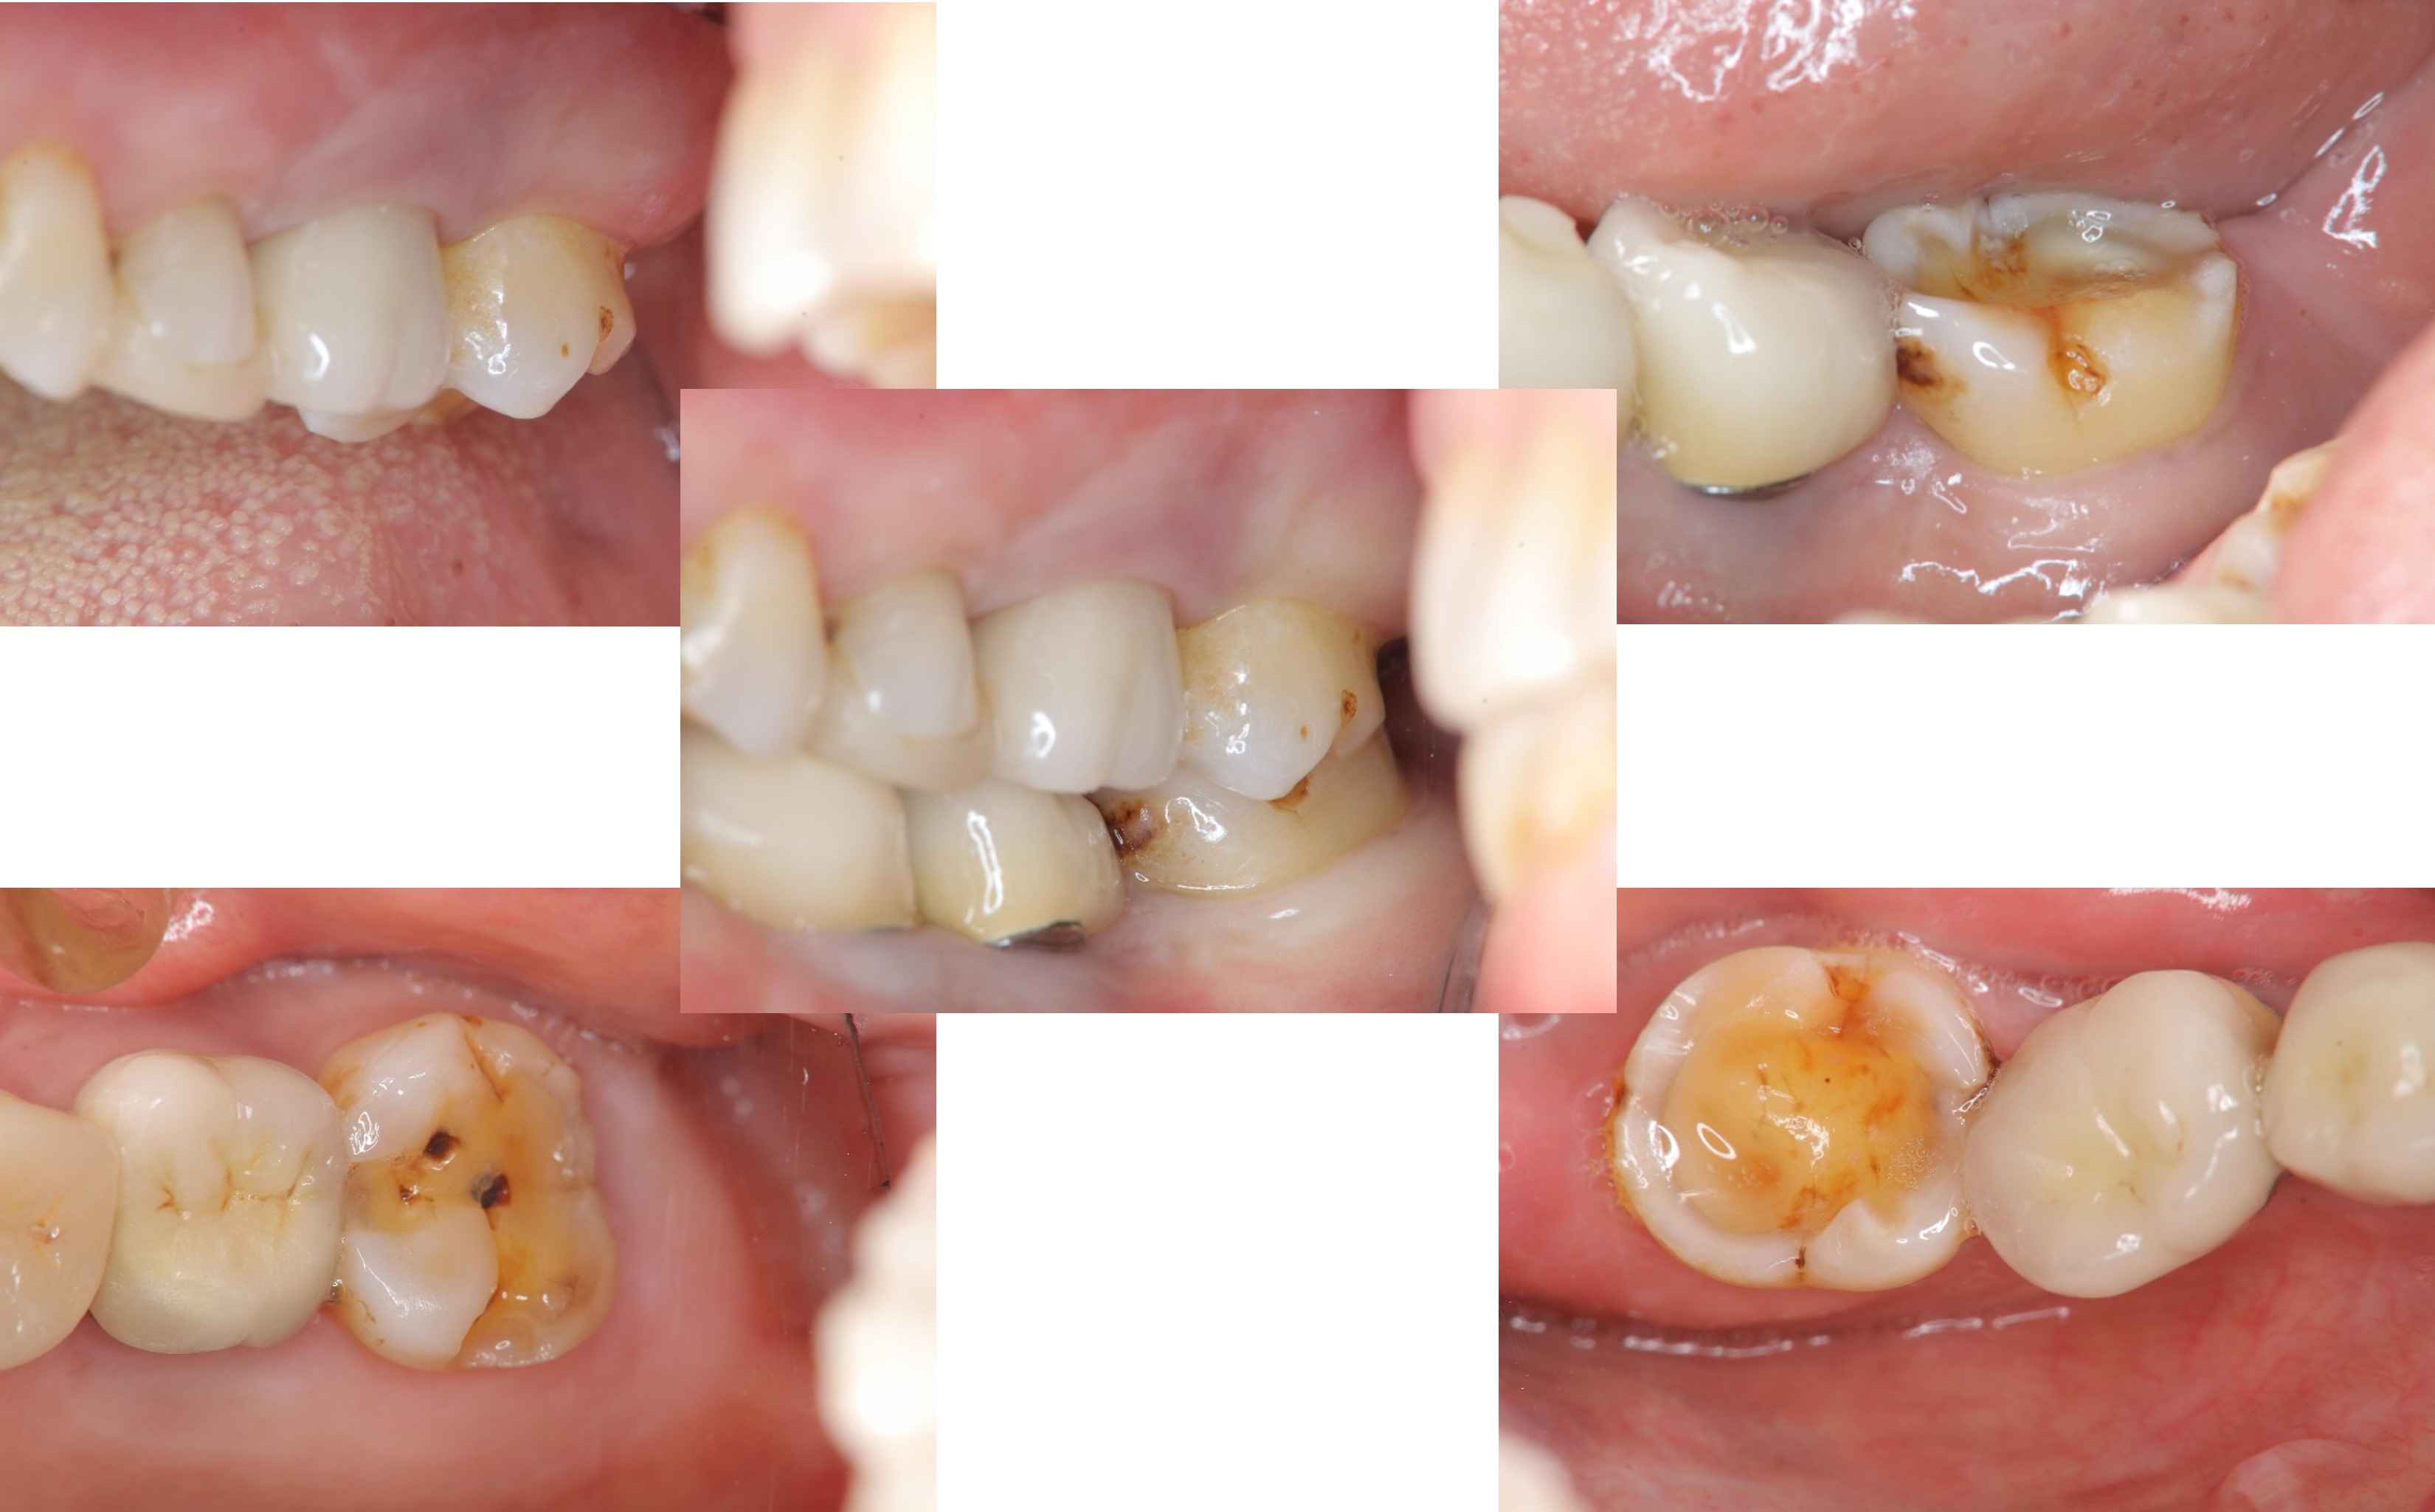

治療前,左上及左下第二大臼齒磨耗

膺復前評估牙齦、牙齒狀態